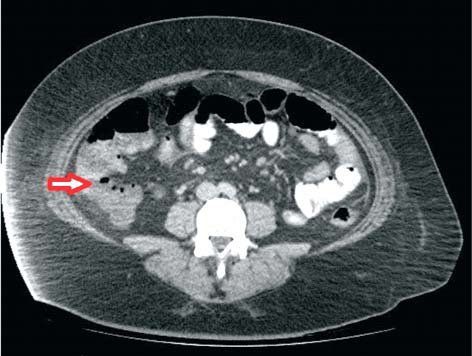

Following features on CAT scan are indicative of acute appendicitis: - dilated appendix with diameter of more than 0.6 cm - thickened wall of appendix > 0.2 mm - stranding of mesenteric fat - appendicolith may or may not be present - peri-intestinal fluid Reference: https://www.ncbi.nlm.nih.gov/pmc/articles/PMC5181572/#:~:text=CT%20findings%20of%20acute%20appendicitis,but%20it%20can%20also%20mislead. Image via: https://www.researchgate.net/publication/335604115_Appendicular_Neuroendocrine_Neoplasm_is_Associated_with_Acute_Appendicitis_-_Don%27t_Miss_the_Boat/figures?lo=1&utm_source=google&utm_medium=organic